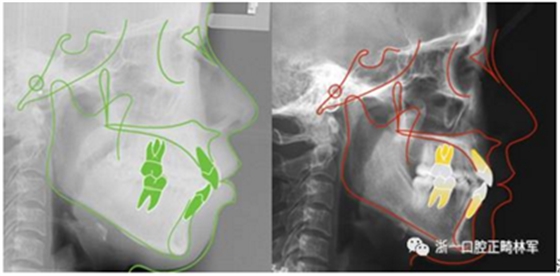

治療前后頭影測量重疊圖(綠色治療前,紅色治療后)